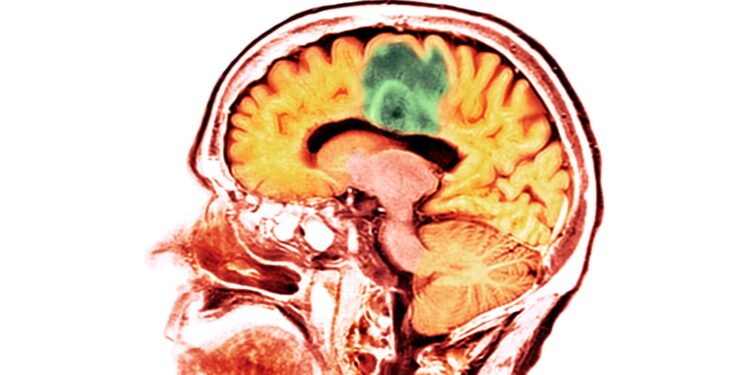

A brand new examine reveals that adults who’ve suffered a moderate-to-severe traumatic mind damage usually tend to develop mind most cancers.

Zafonte’s group examined greater than 150-thousand civilian adults throughout three well being techniques, making this the biggest and most diverse examine to this point a attainable connection between mind tumor improvement and a historical past of TBI. They discovered that whereas sufferers with a gentle TBI weren’t related to a better threat for mind most cancers, sufferers who suffered a reasonable to extreme TBI have been 50% extra prone to develop a malignant mind tumor.

“Why moderate-to-severe TBIs enhance the chance of tumors isn’t well-understood,” Zafonte says. “This could possibly be due to disruptions in metabolic processes or a rise in inflammatory responses within the mind and nervous system.”

These findings might current a chance to determine mind tumors earlier. Sufferers with a medical historical past of a TBI could possibly be screened for tumor development, and the early detection of most cancers would make it way more treatable and consequently enhance affected person outcomes. The examine didn’t distinguish between various kinds of malignant mind tumors, although, and presents a analysis alternative to see if there’s a particular sort linked to TBIs.